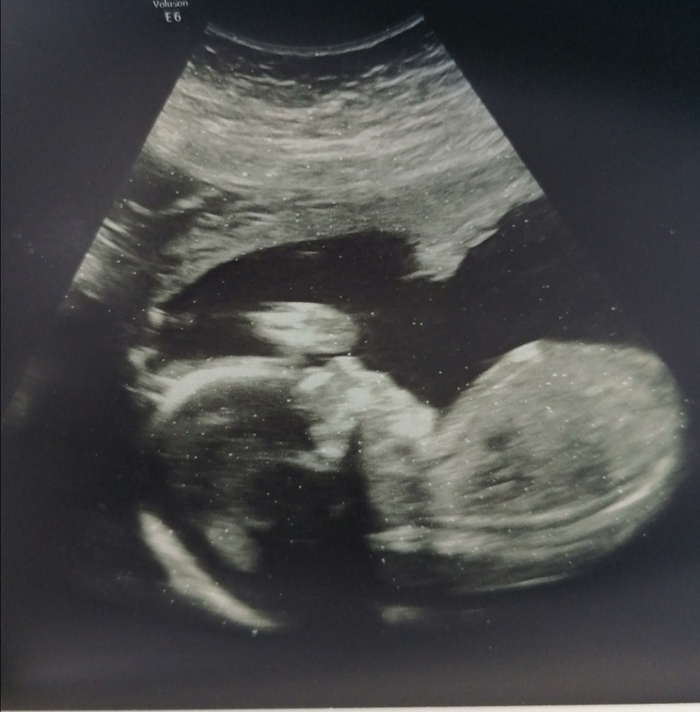

Ровно четыре месяца назад путем Экс появилась на свет Юлиана. Вес нормальный, 3750,хотя узи перед кесаревым обещало 4500)